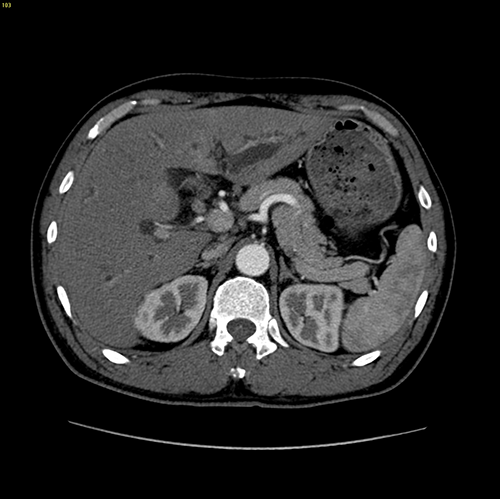

高位胆管癌-胆管癌根治(左半肝+尾状叶切除、右肝管胆肠吻合